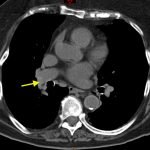

Non-contrast CT of the chest demonstrates hyper-densities within both central and sub-segmental pulmonary arteries bilaterally (see yellow arrows). The right ventricle is dilated.

The diagnosis of pulmonary embolism is usually made by visualizing intravenous contrast filling defects within the pulmonary arteries on CT angiography of the chest. Ventilation perfusion scanning is an alternative modality, but was not available in this case. A hyper-dense lumen sign on non-contrast chest CT1 can identify pulmonary emboli with a reported sensitivity of 36%.2

Utilizing non-contrasted CT of the chest to identify hemodynamically significant central thrombi when IV contrast is not an option may allow for initiation of therapy in a timely manner or may help identify PE when it may not be the primary consideration.